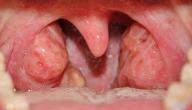

إزالة اللوزتين أو استئصال اللوزتين (Tonsillectomy) تتم فيها إزالة للوزتين بشكلٍ كامل، وقد تكون مصحوبة باسئصال اللحمية (Adenoidectomy) في بعض الحالات.[١]

لجأ الأطباء فيما مضى لعملية إزالة اللوزتين كخيار أوّلي لعلاج حالات العدوى والالتهاب التي تصيب اللوزتين،[٢] أمّا الآن فيتم اللجوء لها غالبًا في الحالات الموضّحة فيما يأتي:

- حالات اضطراب التنفس خلال فترة الليل أو مشكلات التنفس الأخرى المرتبطة بتضخّم اللوزتين، فقد يكون التضخّم في حجم اللوزتين خلْقيًا منذ الولادة، أو ناجمًا عن تكرار إصابة المريض بالعدوى، أو الإصابة بالعدوى التي تستمر لفترة طويلة.[٢]

- التهاب اللوزتين الذي لا يستجيب للعلاج.[٢]

- التهاب اللوزتين الذي يتكرّر حدوثه أكثر من 6 مرات في السنة الواحدة.[٣]

- حالات الإصابة بأمراض أو مشكلات نادرة في اللوزتين، ومنها:[٢]نمو النسيج السرطاني في إحدى اللوزين أو في كلتيهما.